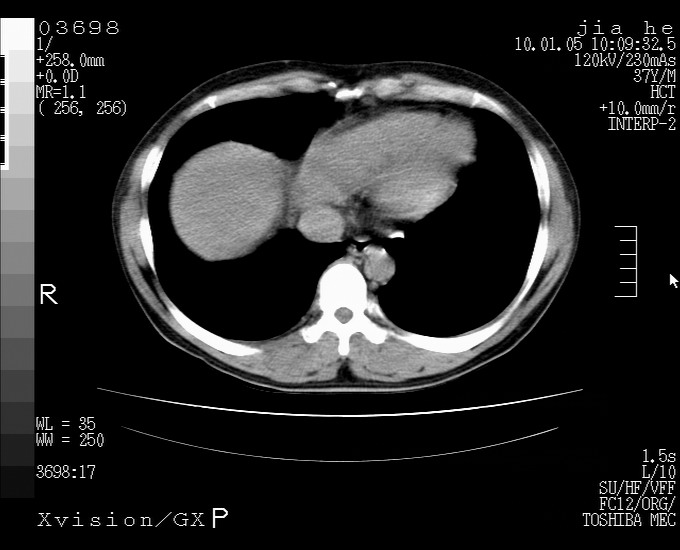

标题: CT23988:男,40岁,B超提示腹部肿物,请各位老师给看看。 [打印本页]

标题: CT23988:男,40岁,B超提示腹部肿物,请各位老师给看看。

考虑肝癌 请强化

肝癌并腹膜后淋巴西结转移

3.肝左叶巨大站位,并腹腔淋巴结肿大,肝癌或肝间叶来源恶性肿瘤,也不排除大网膜间质瘤侵及肝左叶

外生性肝癌并腹膜后淋巴西结转移!

考虑肝左叶外侧段癌并腹膜后淋巴结转移.建议增强进一步检查.